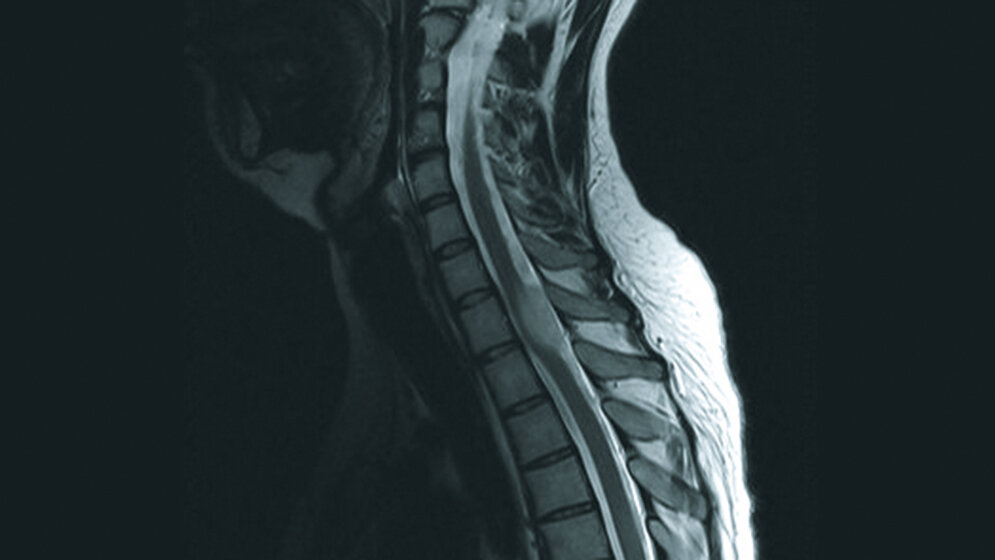

Tumoröse Veränderungen: Spinales Astrozytom

Die Behandlung und Prognose der spinalen Tumoren hängt zu einem großen Teil von der Histologie ab. Um residuale neurologische Defizite so gering wie möglich zu halten, ist eine frühzeitige Diagnose und Therapie neoplastischer und demyelinisierender Myelonveränderungen wichtig. Ein MRT der Neuroachse sollte in Fällen eines Hydrozephalus ohne entsprechende Veränderung durchgeführt werden. Für Radiologen und Neurochirurgen ist es wichtig, nicht-tumoröse und neoplastische Prozesse des Rückenmarkes zu erkennen und zu differenzieren.